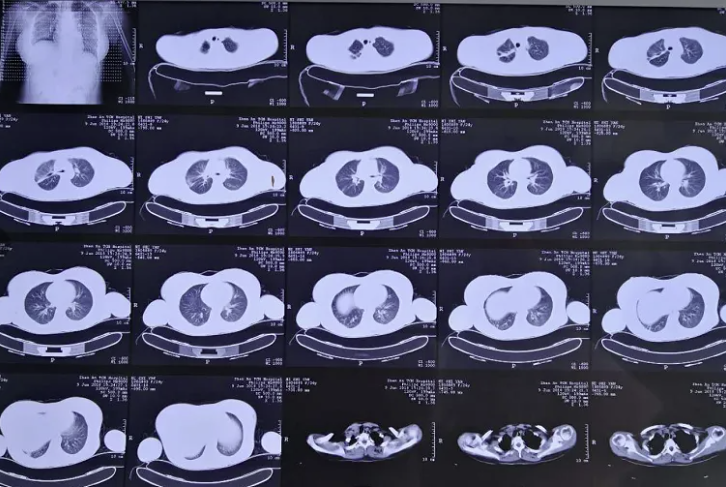

2. 病理学反复验证:首次病理未见明确真菌菌种,2018.01.16复查胸CT:右肺上叶病灶较前明显增大,2018.01.18再次支气管镜检查,镜下表现持续恶化,决定重复支气管镜活检,重点取材坏死组织和黏膜交界处。

图4:2018.01.16胸CT